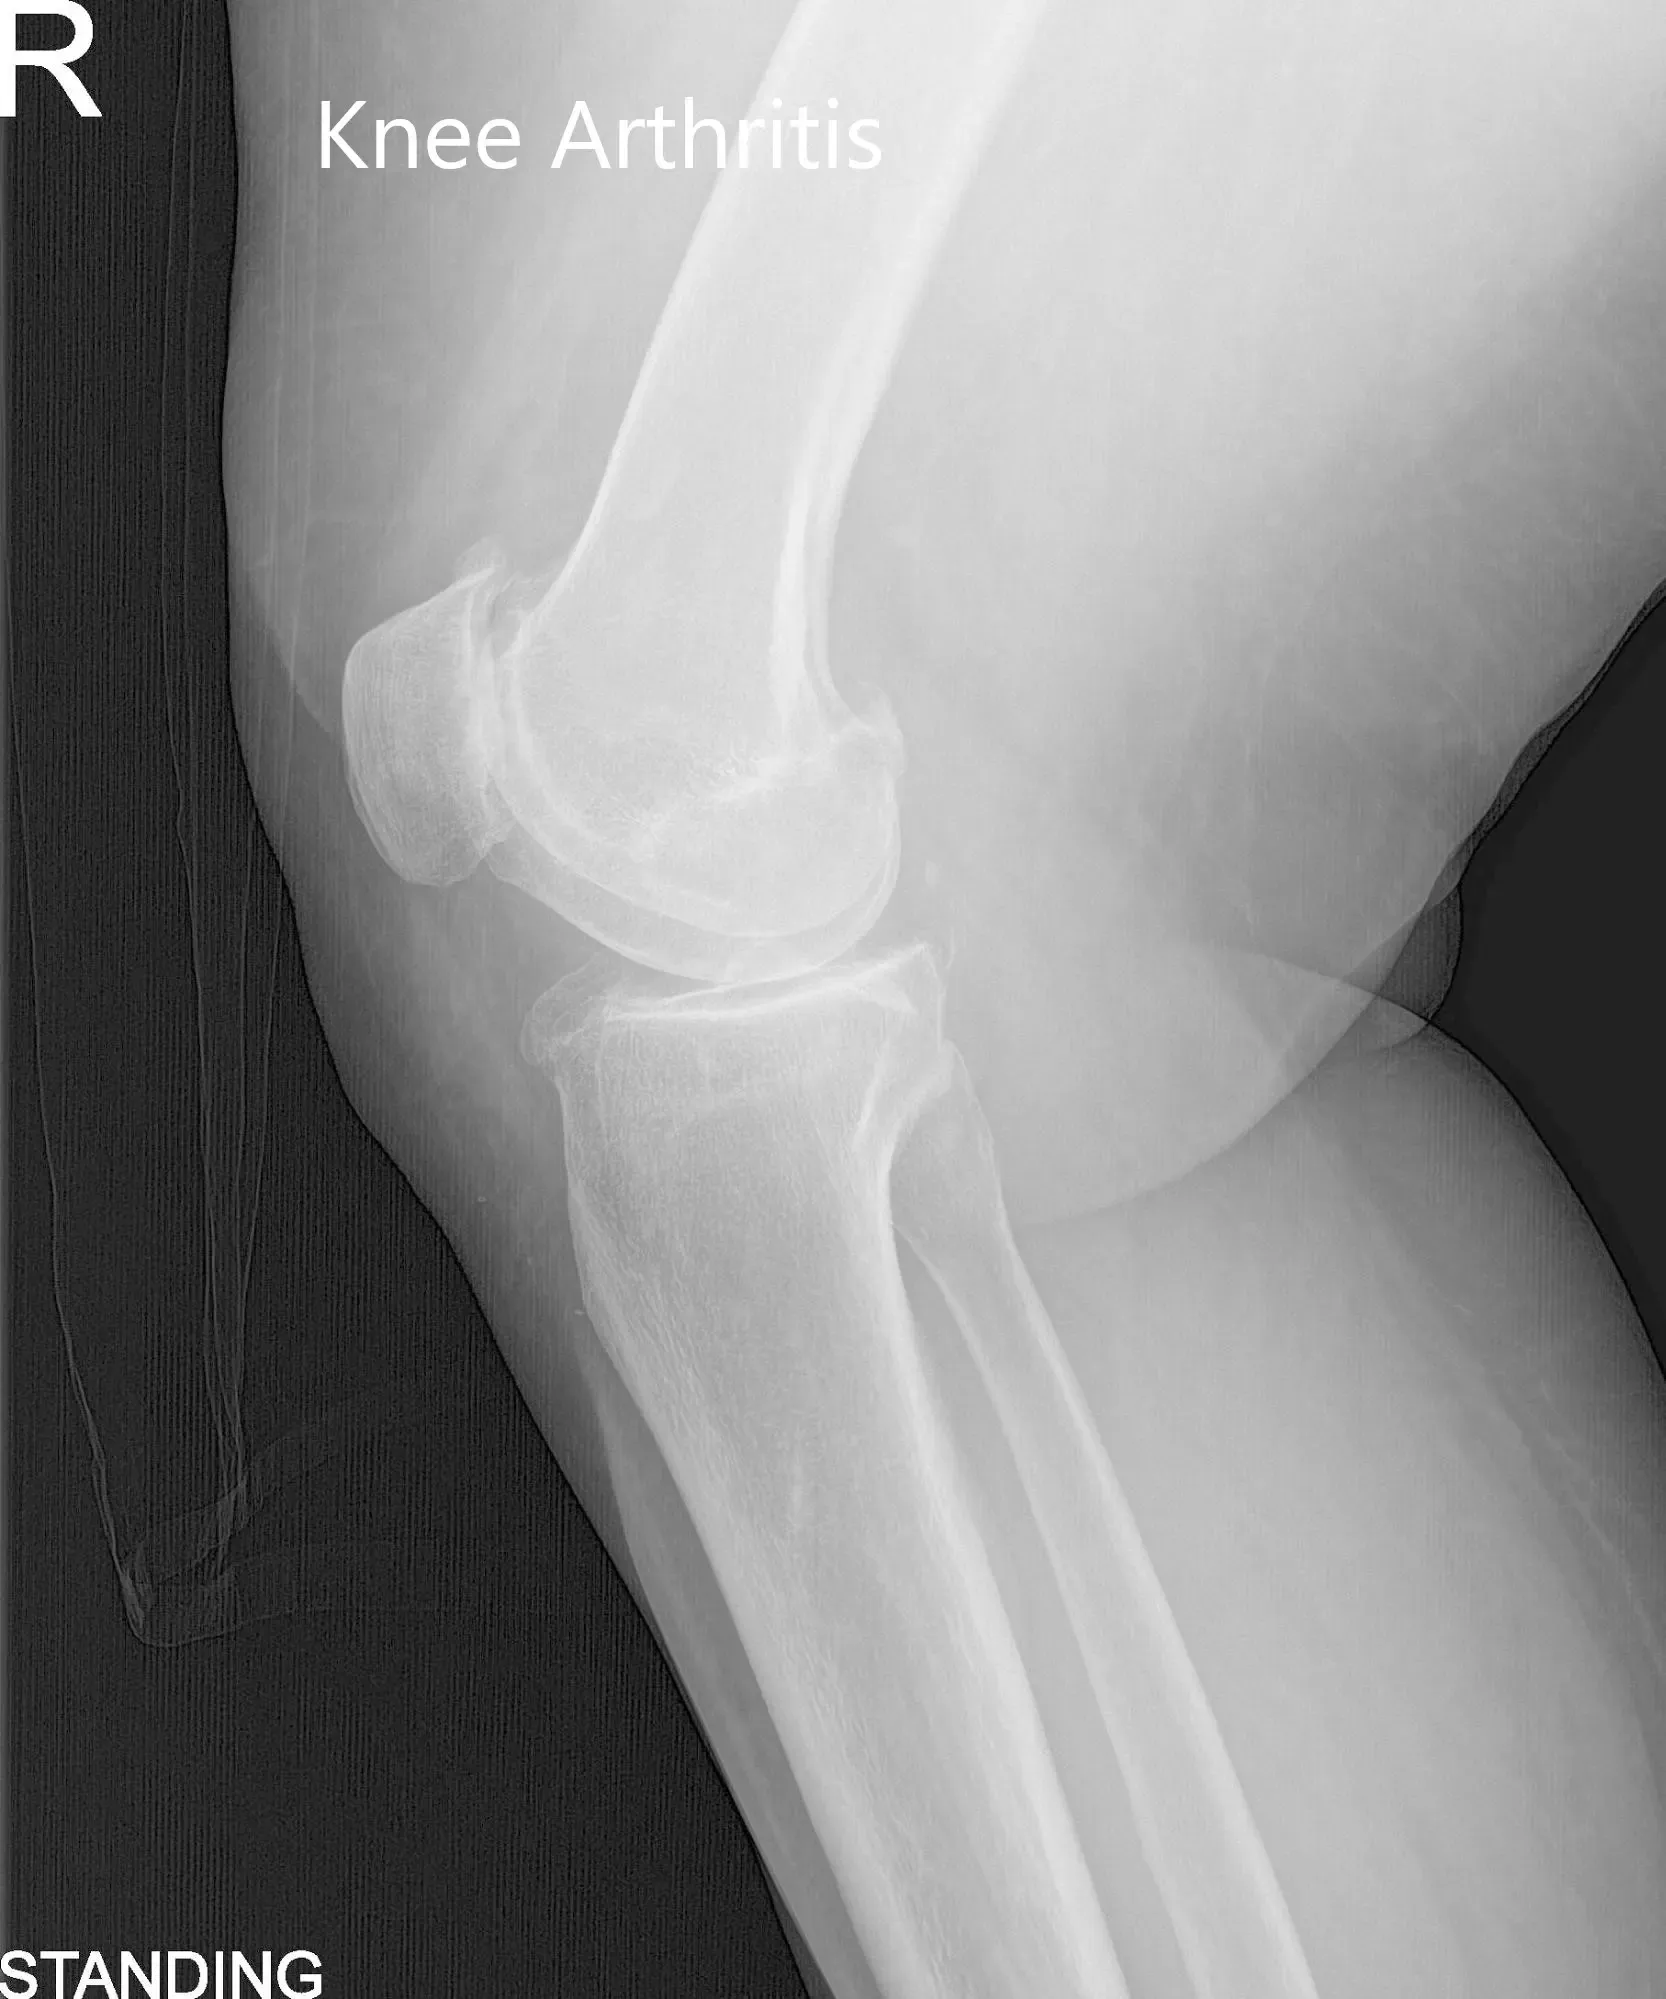

El examen físico reveló una deformidad genu-varo y una ligera inflamación en la articulación de la rodilla derecha. Hubo una crepitación articular marcada en todo el rango de movimiento con sensibilidad moderada en las líneas articulares medial y lateral y sensibilidad en las facetas rotulianas. Los estudios de imagen revelaron un estrechamiento marcado del compartimento articular medial y del compartimento articular patelofemoral con formación moderada de osteófitos.

Vistas preoperatorias de la rodilla derecha (de pie)